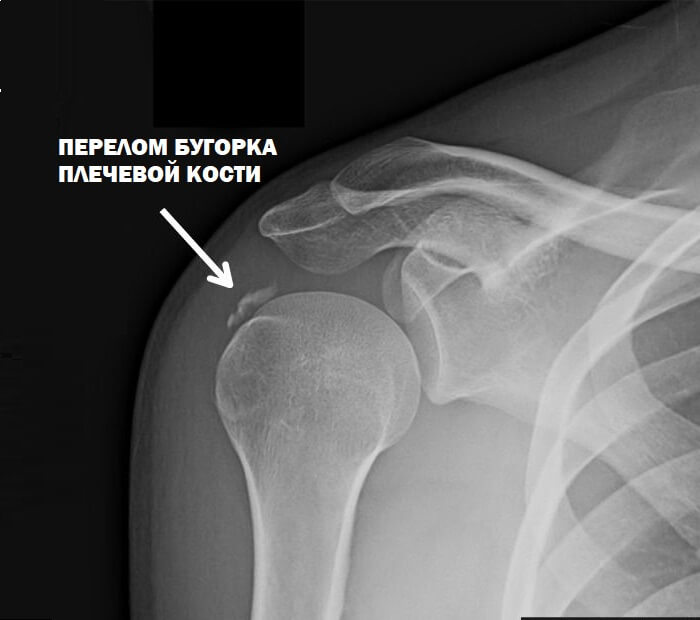

Расположение большого бугорка — наружная сторона плечевой поверхности возле сустава.

Клиническая картина перелома бугорка не различается от иных травм проксимального участка. Для определения диагноза больной направляется в медицинское учреждение для рентгенологического обследования.

Затем пациент направляется в рентген кабинет, для установки диагноза. По результатам обследования определяется метод лечения.

Что такое перелом большого бугорка плечевой кости?

Перелом большого бугорка плечевой кости — это травма выступа, расположенного в верхней части плечевой кости, над головкой.